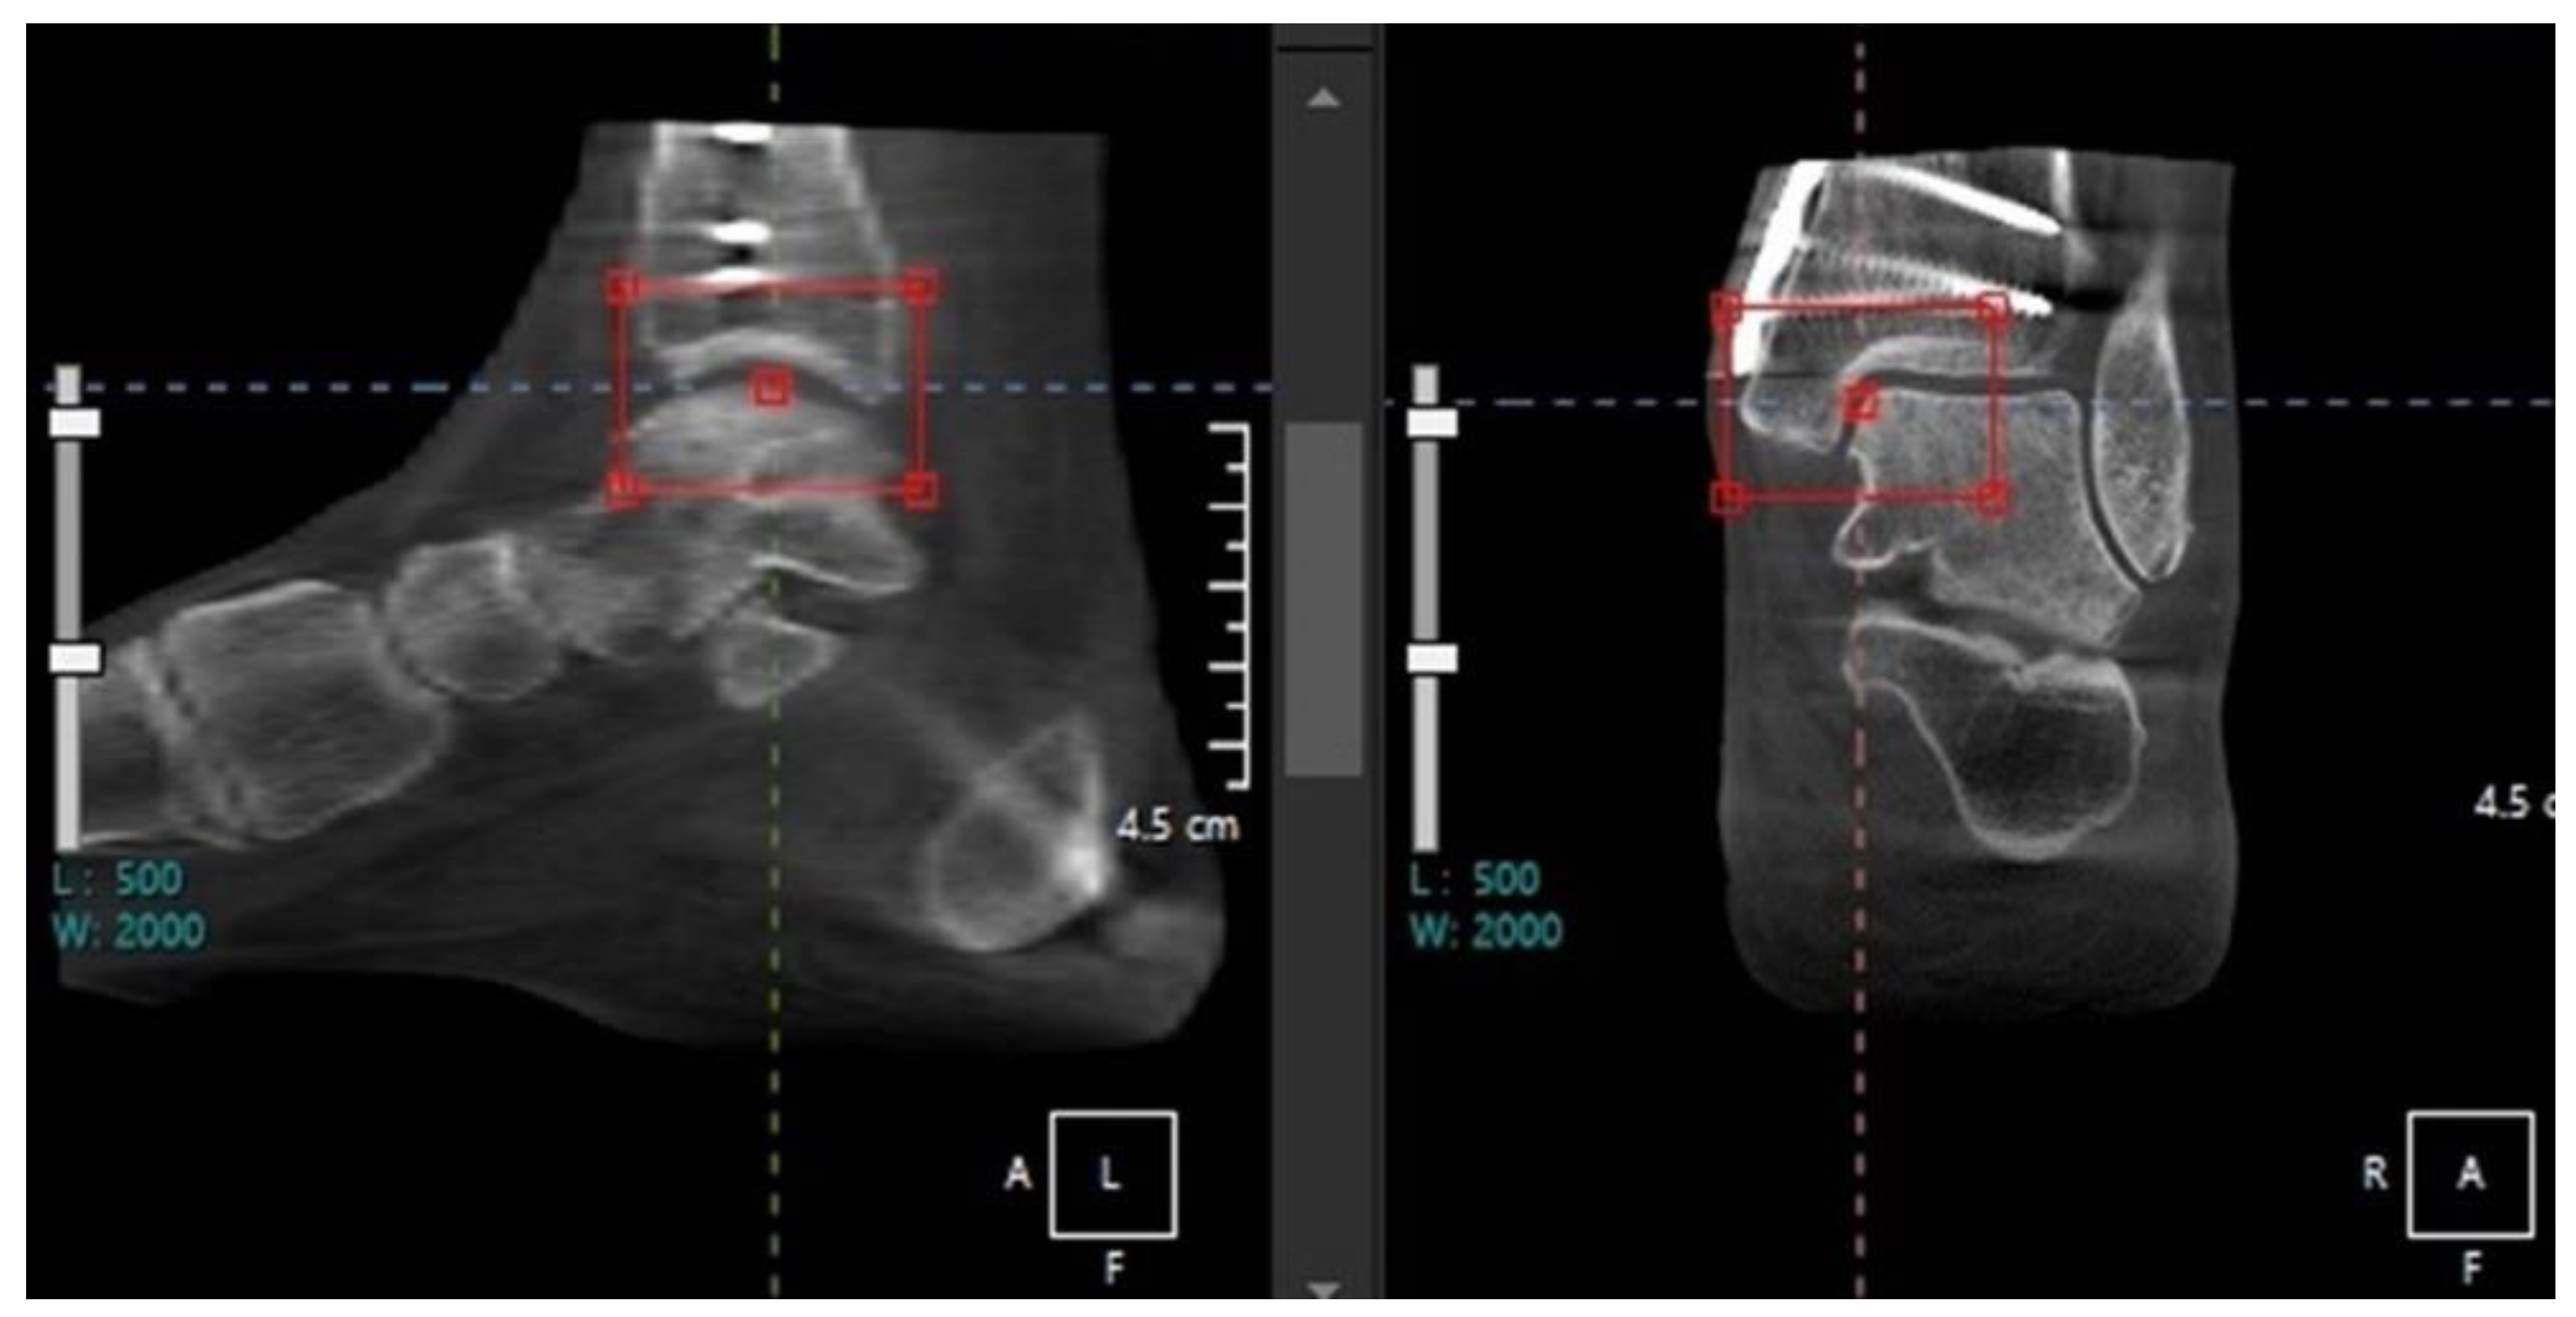

- Osteochondral lesion of talus

- Walley, K.C.; Gonzalez, T.A.; Callahan, R.; Fairfull, A.; Roush, E.; Saloky, K.L.; Juliano, P.J.; Lewis, G.S.; Aynardi, M.C. The Role of 3D Reconstruction True-Volume Analysis in Osteochondral Lesions of the Talus: A Case Series. Foot Ankle Int 2018, 39, 1113–1119. [Google Scholar] [CrossRef]

- Efrima, B.; Dahmen, J.; Barbero, A.; Benady, A.; Maccario, C.; Indino, C.; Kerkhoffs, G.; Usuelli, F.G. Enhancing precision in osteochondral lesions of the talus measurements and improving agreement in surgical decision-making using weight-bearing computed tomography and distance mapping. Knee Surg Sports Traumatol Arthrosc 2024. [Google Scholar] [CrossRef]